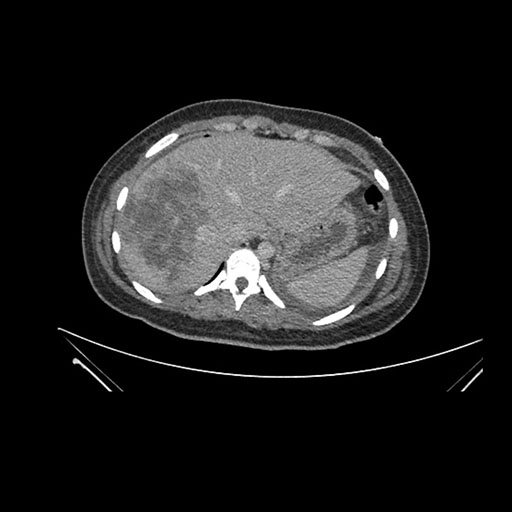

Axial Arterial

Axial Venous